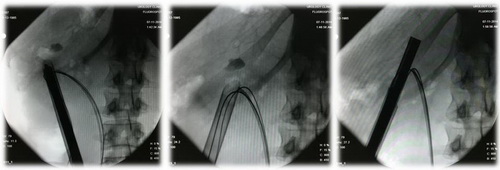

Рис. Рентгенологические этапы операции.

Видео. Операция: Чрескожная нефролитотрипсия. Хирург: доктор медицинских наук Акопян Г.Н.